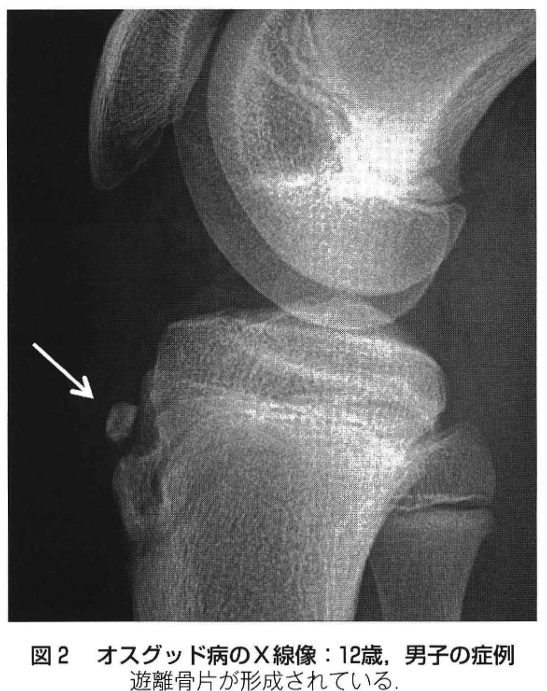

成長期の膝関節周辺に発生するスポーツ障害で最も代表的な疾患はオスグッド病です。膝の脛骨粗面というところが膝蓋腱によって引っ張られることで生じる膝伸展機構障害の一つです。成長期障害の特徴である患部の脆弱性や急激な身長増加による筋柔軟性低下を背景とし、そこに動作不良や運動量増加による患部への伸張ストレスが加わることが発症の一因となっていると考えられます。好発は10歳から14歳の男子で、30%が両側発症します。

診察では上の図のようなひざ下の骨の隆起を確認し、痛みの有無をチェックします。単純X線像で脛骨粗面部の不整な隆起像、遊離骨片がみられる場合、診断は比較的簡単です。しかし発症初期から進行期の場合はX線で脛骨粗面の変化を捉えることは困難であり、MRIや超音波検査が診断に有用であります。

発育期に生じるオスグッド病は、身長の急伸により大腿四頭筋の過緊張が生じ、脛骨粗面および膝蓋骨に大きな牽引力が加わることによって発症すると考えられています。初期の症例では、自発痛は軽く、運動終了後の違和感や、熱感脛骨粗面の腫脹などがみられます。運動時の強い痛みの出現は進行期からで、終末期に到ると脛骨粗面の腫脹や隆起が著明となり、痛みや圧痛も遷延します。

初期または進行期の場合、スポーツの休止または別メニュートレーニングを指示します。特に遊離骨片の形成が明らかでない場合は、終末期に進展させないために、患部の安静の指導をすべきです。遊離骨片を形成せずに分離部が癒合すれば、比較的短期間で(2カ月程度)スポーツ活動を再開できます。これに対して診断時にすでに遊離骨片を形成し慢性的な痛みをもつ場合は、スポーツ活動中の違和感や痛みは長期間続くことが多いです。このような症例には局所のアイスマッサージ、非ステロイド系消炎鎮痛剤の外用、オスグッド用のサポーターの使用、下肢のストレッチを指導し、可能であればスポーツを継続させてもよいと考えます。身長の伸びが終息し、残存した遊離骨片周囲の炎症や滑液包炎などで疾痛が続く場合は、遊離骨片の摘出や骨棘切除術が行われる場合があります。